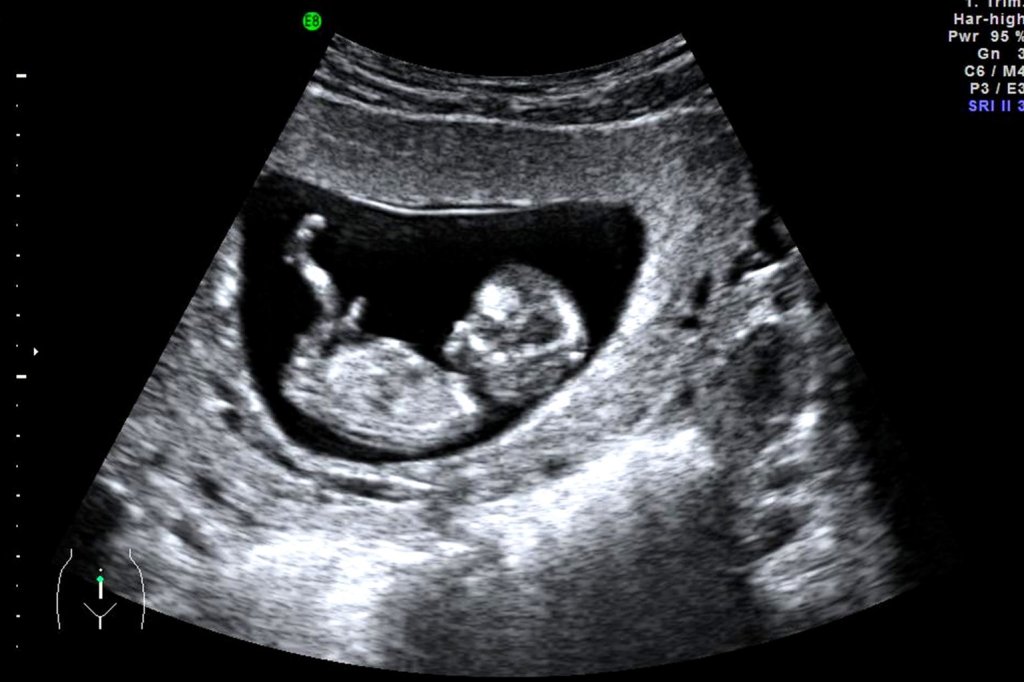

As a woman approaches her twelfth week of pregnancy, she is usually preparing for her first antenatal visit with her midwife, at which she will have her first ultrasound scan and shortly after that visit she will happily make her first announcements to family, friends, and maybe even to her employer. By this stage of pregnancy, the baby is fully formed, all the organs, muscles, limbs, bones, fingers, and toes are in place, and the sex organs are well developed.

In Scotland in 2020, there were 1,707 abortions at gestational ages of more than 10 weeks. More than 800 of these were performed by the woman herself at home, using the PHS officially approved EMAH (Early Medical Abortion at Home) procedure. That is more than two women each day, choosing to end the life of their baby at a stage of development when the baby is fully formed, needing only to continue growing and maturing before his/her natural birth. By the end of this permitted period, 11 weeks and six days, the baby is about 7.5cm long and weighs about 18g, so they would certainly be visible and identifiable when passed by their mother under the contractions caused by the misoprostol; little wonder then that abortion providers advise women to sit on the toilet and to flush without looking.